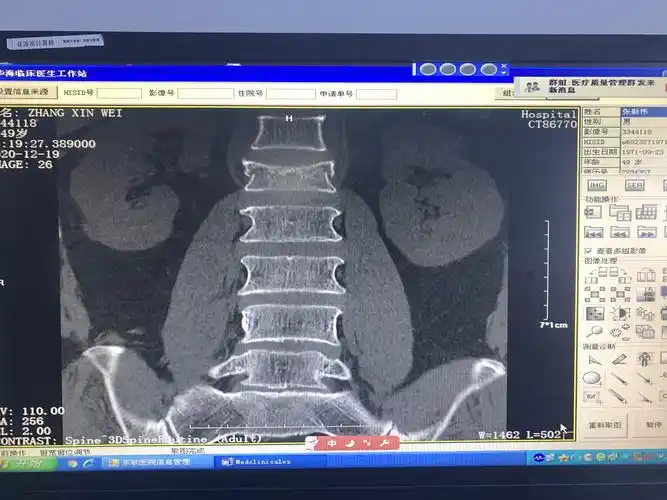

腰1椎体爆裂性骨折,腰1 2 3双侧横突骨折

术前dr示腰1椎体压缩骨折

腰椎爆裂骨折并脊髓损伤 - 好大夫在线